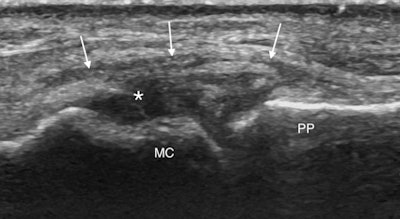

In an undisplaced tear in which the ligament looks thickened and hypoechoic often with a cleft extending through it, there is no significant proximal retraction, so the ligament appears symmetrically centered over the MCP joint. Dynamic imaging once again using joint extension and flexion will show the aponeurosis gliding over the thickened hypoechoic torn ligament. Meanwhile, in Stener lesions the torn ligament retracts proximal to the MCP joint to lie adjacent to the metacarpal head. The ligament has an asymmetrical appearance with a larger retracted proximal end, which looks like a round hypoechoic mass.

"The adductor aponeurosis will point into the retracted ligament and does not overlie it. This nodular appearance recalls the 'yo-yo on a string' sign visible at MRI with the aponeurosis making up the string extending into the retracted nodular ligament, which forms the ball of the yo-yo," McCarthy said. "You may also see the aponeurosis folding between the fibers of the torn ligament which are displaced superficial to the aponeurosis."

Again dynamic imaging will show the aponeurosis clashing into the retracted ligament that is displaced proximal and superficial to the aponeurosis, and this identification method should be preferred to radial stress. It is often useful to compare with the normal asymptomatic side to help clarify the picture and confirm the diagnosis, while keeping an eye out for an avulsion fracture, she concluded.